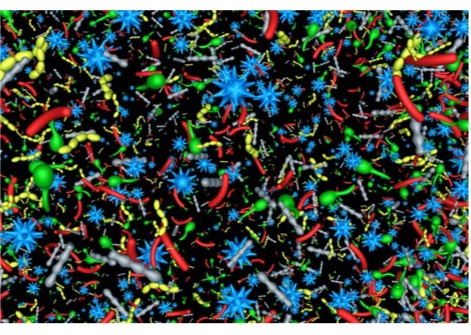

بعد ذلك، حفّز العلماء الخلايا العصبية في أنسجة دماغ الفأر باستخدام أسلوب التزجيج والتجميد، ولاحظوا أماكن اندماج الحويصلات المشبكية مع أغشية خلايا الدماغ، ثم إطلاق مواد كيميائية تُسمى النواقل العصبية، والتي تصل إلى خلايا الدماغ الأخرى. ثم لاحظوا كيف تُعيد خلايا دماغ الفأر تدوير الحويصلات المشبكية بعد استخدامها في التواصل العصبي، وهي عملية تُعرف باسم الالتقام الخلوي، والتي تسمح للخلايا العصبية بامتصاص المواد.

في عينات دماغ كل من الفأر والإنسان، كان بروتين Dynamin1xA، وهو ضروري لإعادة تدوير غشاء التشابك بسرعة فائقة، موجودًا في المناطق التي يُعتقد أن عملية الالتقام الخلوي تحدث فيها على غشاء التشابك.